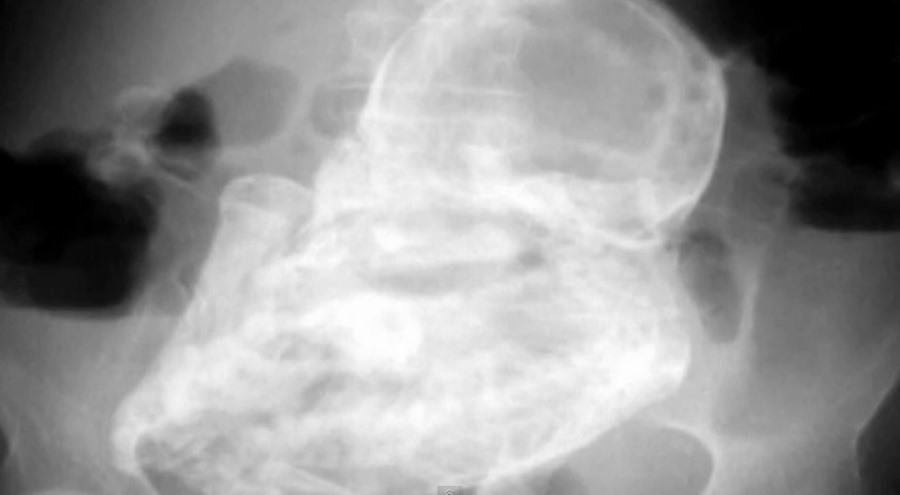

Robyn Benson, 32-godišnja žena iz Vancouvera u Kanadi čija je tužna priča pogodila svijet, rodila je i na svijet donjela zdravog dječaka Iver Cohen Bensona. Iako je rođen u 28. tjednu dobro je. Otac se raduje, ali i tuguje jer je postao udovac - njegovu suprugu doktori su održavali na životu putem aparata kako bi njeno tijelo iznijelo trudnoću koju je zasjenila njena iznenadna bolest.